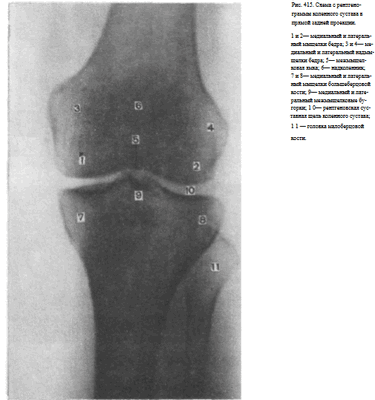

СНИМКИ КОЛЕННОГО СУСТАВА В ПРЯМОЙ ПРОЕКЦИИ

Назначение снимка. Рентгенографию коленного сустава производят во всех случаях заболеваний сустава и при травмах.

Укладки больного для выполнения снимков. Существует несколько вариантов укладки для выполнения этого снимка:

1. Чаще всего рентгенографию коленного сустава производят в прямой задней проекции. При этом больной лежит на спине, обе ноги вытянуты, сагиттальная плоскость стоп расположена перпендикулярно к плоскости стола. Кассету размером 18 х 24 см располагают в продольном положении. Проекция суставной щели, находящаяся при вытянутой ноге на 1,5—2 см ниже нижнего полюса надколенника, легко прощупываемого под кожей, соответствует средней линии кассеты. Пучок рентгеновского излучения направляют отвесно на центр кассеты (рис. 411).

Информативность снимка. На снимке коленного сустава в прямой задней проекции определяются дистальный метаэпифиз бедренной кости, медиальный и латеральный мыщелки бедра, между которыми располагается межмыщелковая ямка. Выше мыщелков определяются медиаль-ный и латеральный надмыщелки. На фоне дистального метаэпифиза бедренной кости виден надколенник. Проксимальный эпифиз большеберцовой кости представлен медиальным и латеральным мыщелками, между

которыми определяются медиальный и латеральный межмыщелковые бугорки. На латеральный отдел метаэпифиза большеберцовой кости частично накладывается головка малоберцовой кости. Между мыщелками бедренной и большеберцовой костей выявляется рентгеновская суставная щель коленного сустава в виде неравномерно изогнутой полосы просветления (рис. 415).

Информативность снимков коленного сустава как в задней прямой, так и в передней прямой проекциях одинаковая. В передней прямой проекции несколько лучше видна структура надколенника. Информативность одномоментных снимков коленных суставов в прямой задней проекции ниже, так как каждый из суставов при этом подвергается проекционным искажениям.